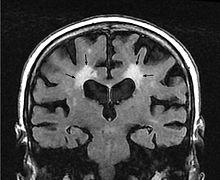

Leukoaraiosis is a particular abnormal change in appearance of white matter near the lateral ventricles. It is often seen in aged individuals, but sometimes in young adults.[1][2] On MRI, leukoaraiosis changes appear as white matter hyperintensities (WMHs).[3][4] On CT scans, leukoaraiosis appears as hypodense periventricular white-matter lesions.[5]

The term "leukoaraiosis" was coined in 1986[6][7] by Hachinski, Potter, and Merskey as a descriptive term for rarefaction ("araiosis") of the white matter, showing up as decreased density on CT and increased signal intensity on T2/FLAIR sequences (white matter hyperintensities) performed as part of MRI brain scans.

These white matter changes are also commonly referred to as periventricular white matter disease, or white matter hyperintensities (WMH), due to their bright white appearance on T2 MRI scans. Many patients can have leukoaraiosis without any associated clinical abnormality. However, underlying vascular mechanisms are suspected to be the cause of the imaging findings. Hypertension, smoking, diabetes,[3] hyperhomocysteinemia, and heart disease are all risk factors for leukoaraiosis.